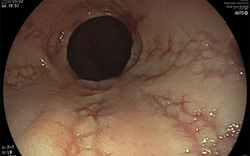

• Đau bụng, đầy hơi, trào ngược dai dẳng - Bác sĩ CKII Vân Anh tiết lộ giải pháp trị từ gốc, hiệu quả bền vững

Đau bụng, đầy hơi, trào ngược dai dẳng - Bác sĩ CKII Vân Anh tiết lộ giải pháp trị từ gốc, hiệu quả bền vững